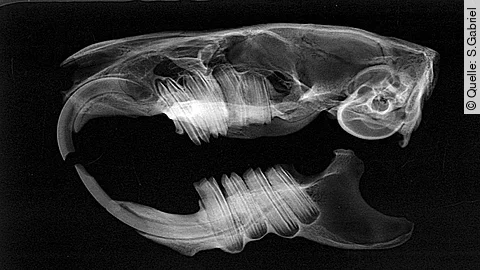

Um Veränderungen und Abnormalitäten der Zähne zu erkennen, sollten die Zahnformeln von Hunde- und Katzenwelpen bekannt sein, sowohl im Milch- als auch im Permanentgebiss. Aber auch die Zeiten der Zahndurchbrüche und -wechsel sind von großer Bedeutung bei der fachgerechten Beurteilung.

Es können verschiedene pathologische Veränderungen bei Hunde- und Katzenwelpen vorhanden sein, dazu zählen Gaumenveränderungen wie Lippen-, Kiefer- oder Gaumenspalte, aber auch Veränderungen der Zähne. Hier kann eine Abweichung der Zahnanzahl nach oben oder unten zu Problemen im Kiefer führen oder auch zum Ausschluss als Zuchttier, dabei ist eine erhöhte Anzahl an Zähnen meist deutlich problematischer und behandlungsbedürftig, hingegen fehlende Zähne für die Gesundheit des Tieres meist weniger von Bedeutung sind. Aber auch Anomalien der Zahnform können auftreten wie beispielsweise die unvollständige Teilung einer Zahnanlage, die Verschmelzung zweier Zahnanlagen, die Verwachsung zweier Zähne oder auch überzählige Wurzeln und viele andere Veränderungen der Zähne. Außerdem können Zahn- und Kieferstellungsanomalien auftreten. Teilweise sind diese rassetypisch und demnach nicht behandlungsbedürftig, jedoch gibt es auch Fehlstellungen, die zu Schmerzen und Schäden führen können und demnach behoben werden sollten.